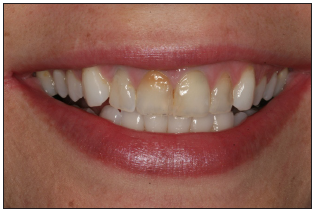

Front smile view

Show a full natural smile. Face should be relaxed. The vertical center of the slide should be the philtrum of the upper lip. Avoid compensating for midline discrepancies.

Confirm that the incisal plane of the maxillary teeth is the horizontal middle of the photo. If patient presents a canted incisal plane, duplicate position in this view. Camera should not be tilted to compensate for canted midline.

Stand directly in front of patient for straight on view. The camera should be 90 degrees to the patient's face. Teeth normally viewed in full natural smile should appear in image. Mandibular teeth may not appear.